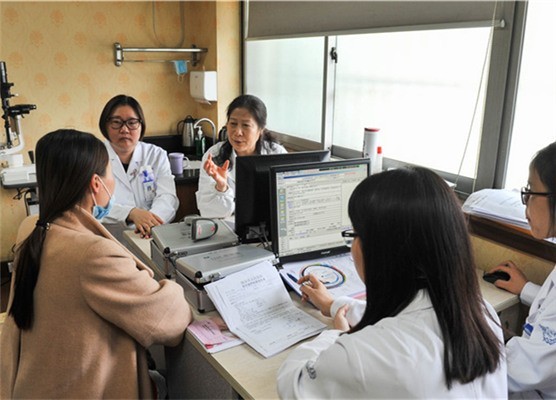

1. 胎儿医学联合门诊介绍

自门诊开展以来,接诊的病种不计其数:胎儿脑积水、脑出血、肾积水、畸胎瘤、多囊肾、唇腭裂、骨发育不良、足内翻、肺囊腺瘤、胸腔积液、先天性心脏病、胎儿宫内生长受限、胎儿全身水肿伴淋巴水囊瘤,双胎一胎胎死宫内,无脑儿,染色体异常……胎儿医学门诊的专家组从产科、新生儿、超声三个角度为孕妇解答胎儿目前的情况,可能的预后以及可行的干预,为孕妇提出最合适的诊疗方案。让我们共同努力,为您拥有一个健康的宝宝,安全渡过整个孕期保驾护航。

相关科室:产科、儿科、超声影像科(翟洪波、黄先玟、包凌云)